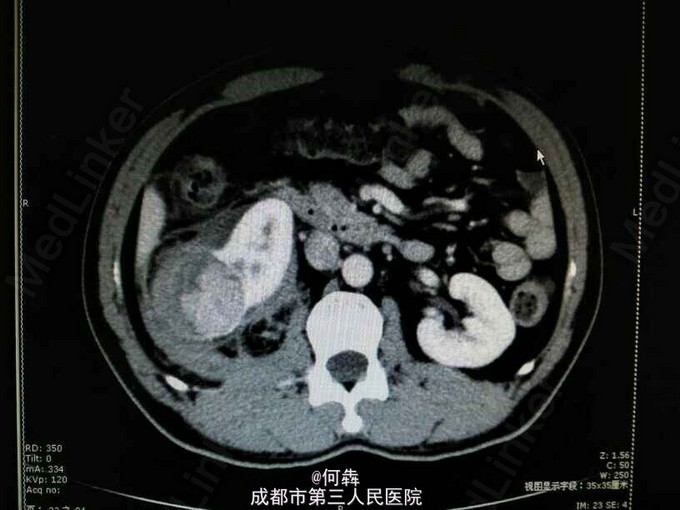

48岁男性,因“突发右腰痛1小时”入院,无血尿、外伤。既往无高血压、糖尿病。

右肾区扣痛阳性,余阴性。

右肾占位伴出血。入院后6天在全麻下行右肾部分切除术。术中冰冻及术后病检见图片

肾上皮样血管平滑肌脂肪瘤(EAML)是肾血管平滑肌脂肪瘤的一种少见亚型。2004版WTO肿瘤分类定义为一种具有恶性潜能的间叶性肿瘤。诊断时则往往与肾细胞癌相混淆。近年较多文献报道,部分EAML易局部复发、侵袭性生长、静脉侵犯、淋巴结或远处转移(以肝和肺转移为主),其预后不佳。